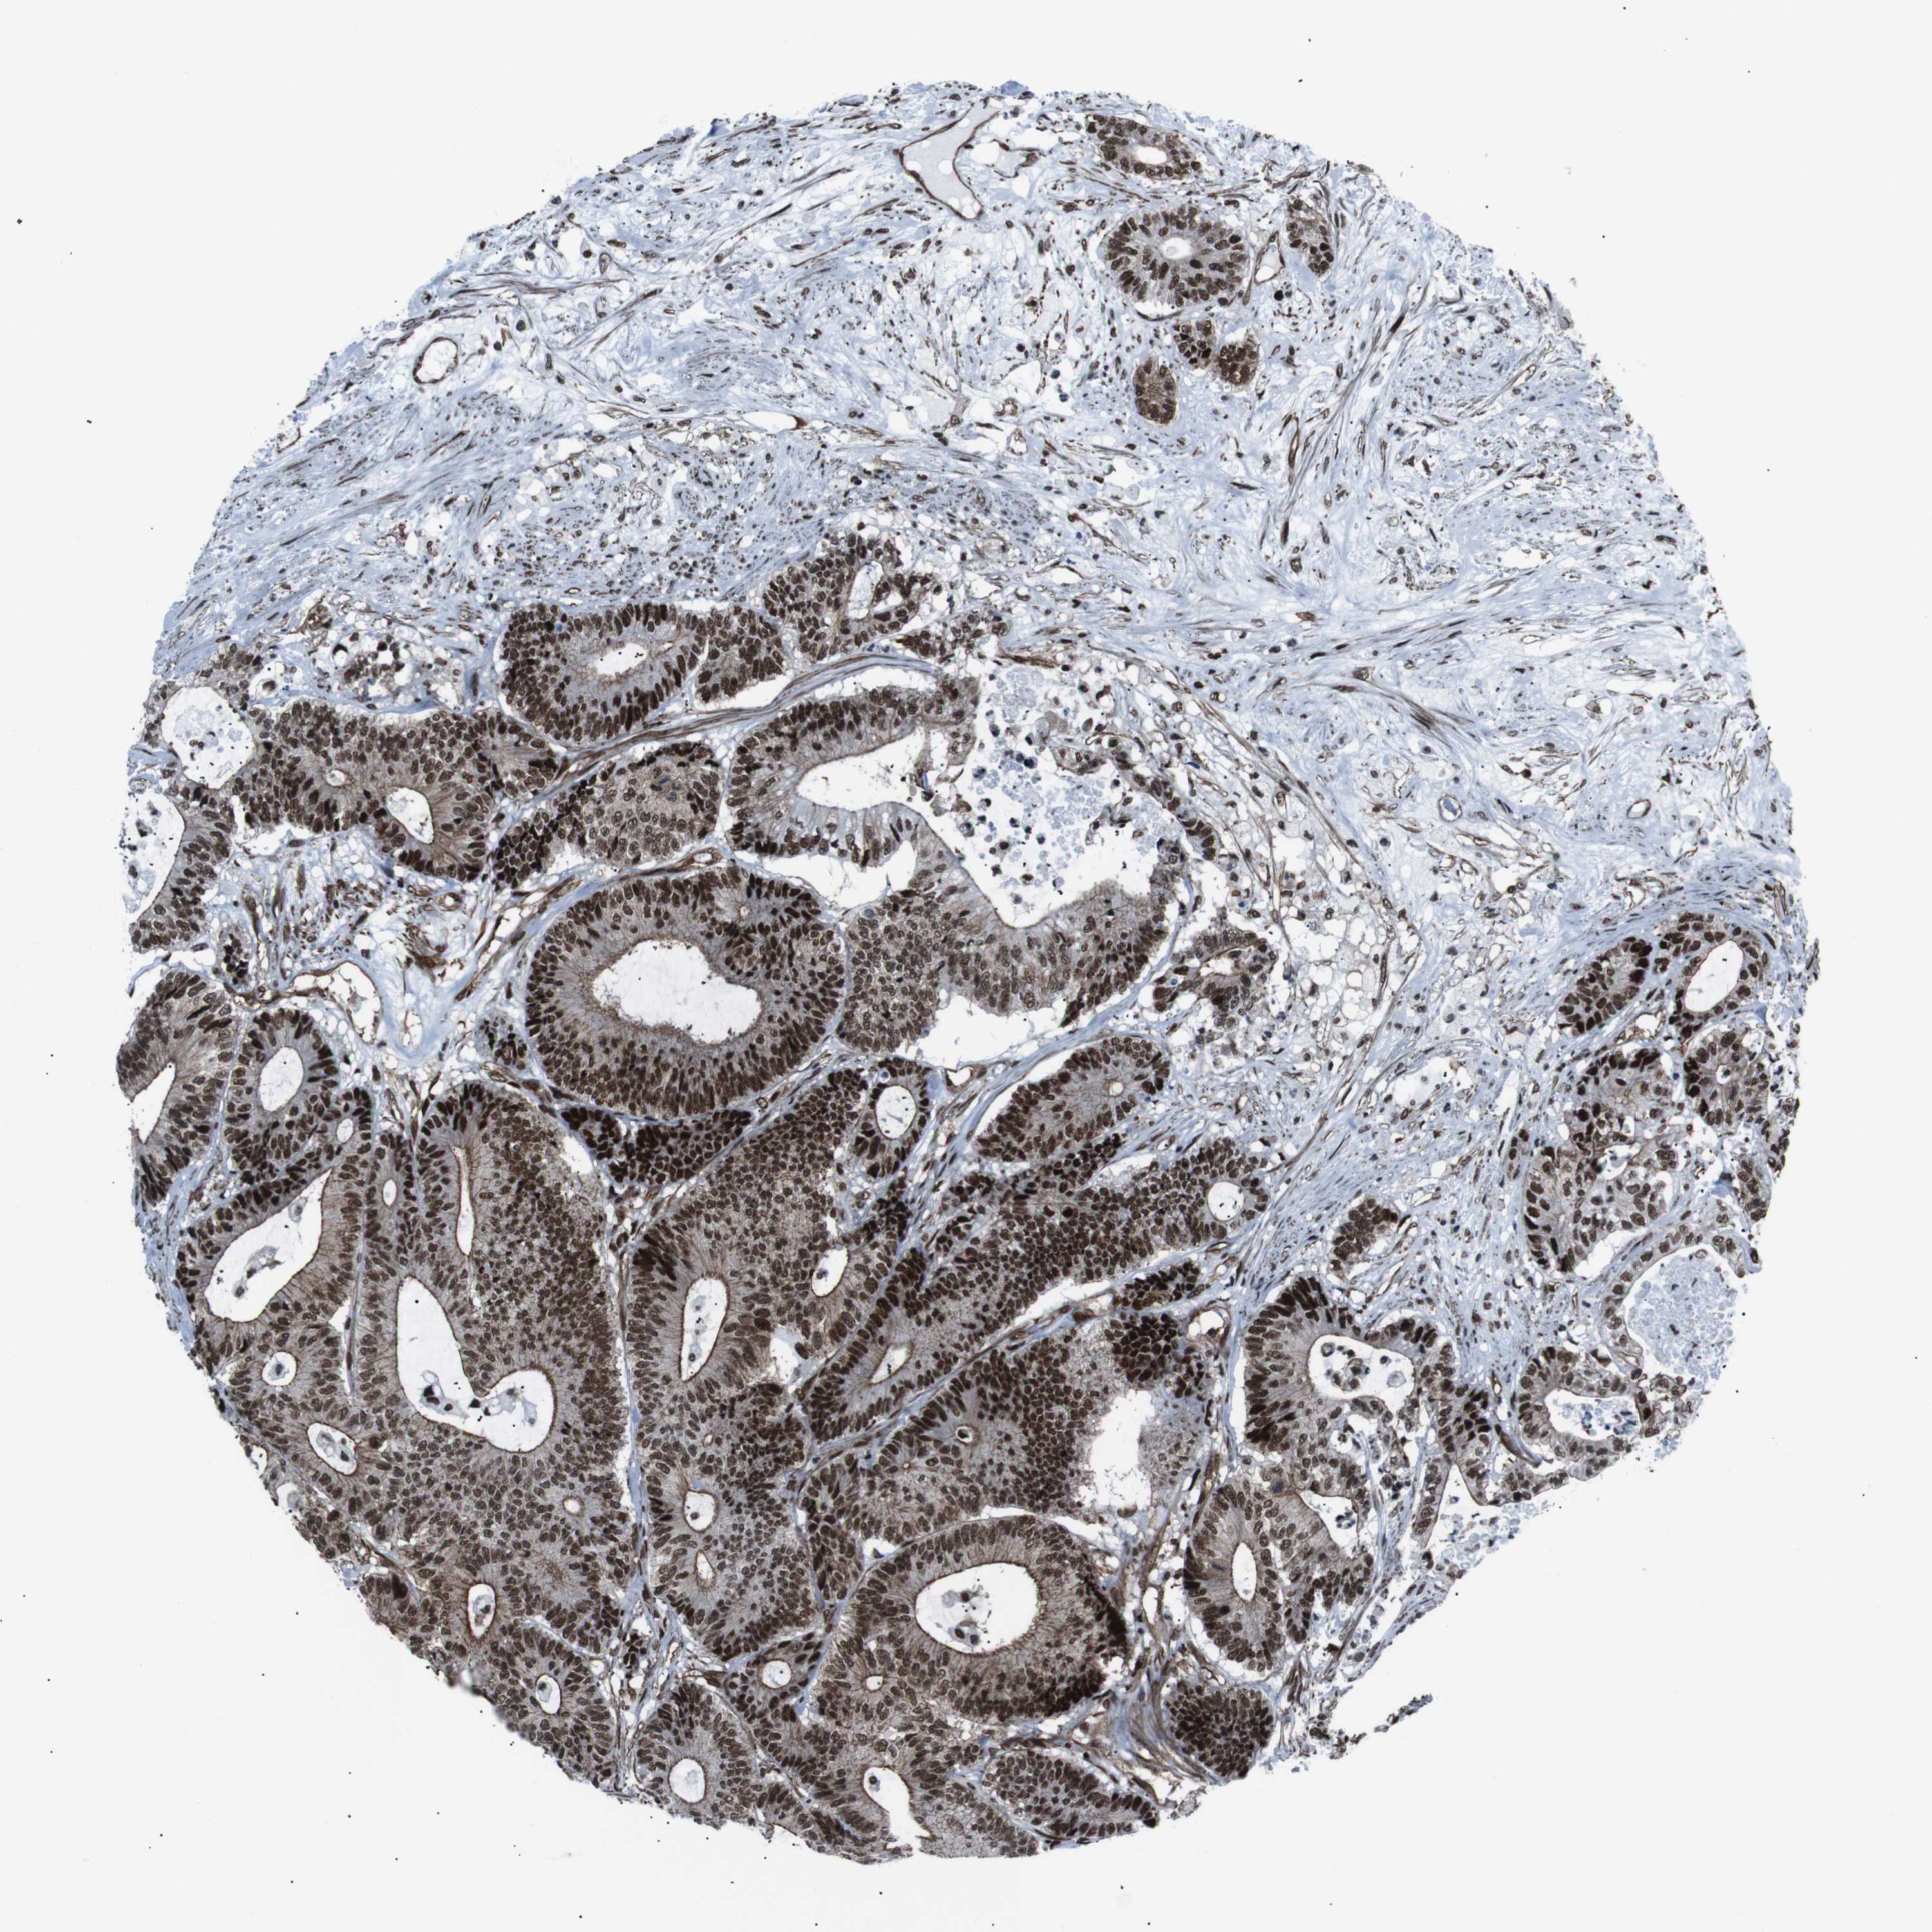

Colorectal cancer

Colon adenocarcinoma